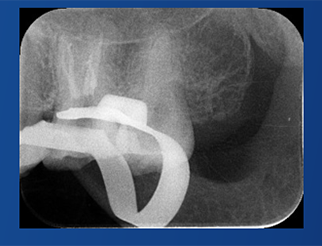

C-Root SP是預混合的、可即刻應用的、可注射的、遇水凝固的硅酸鹽類生物活性陶瓷糊劑材料,主要成分為硅酸鍶、氧化鋯、磷酸鈣、氫氧化鈣,用于根管的密封和永久充填,適合單尖法、側壓法和熱牙膠法。 C-Root SP為世界口腔醫生提供一個“鍶生物陶瓷”的新選擇! >>>

祝自洋老師案例